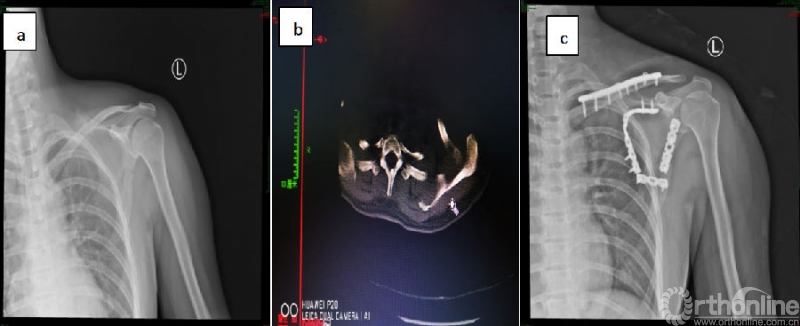

术后复查影像学资料

注:图d为2019.06.18复查的X线片,提示左锁骨远端溶解;图e、f、g为2020.11.30复查的X线、CT、MRI,提示左锁骨远端缺失,核磁压脂像上未见明显的混杂信号。